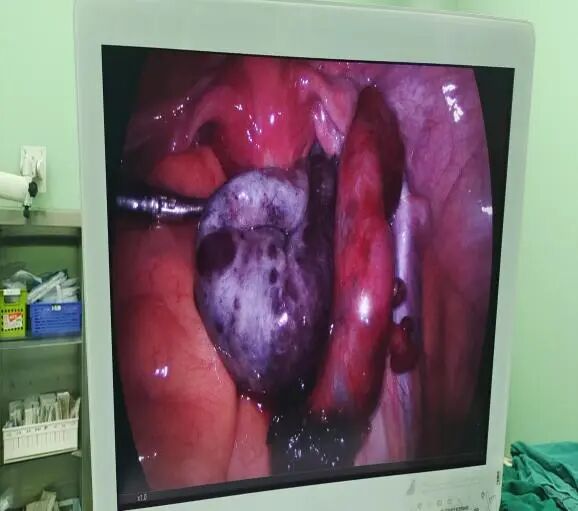

少见!卵巢囊肿蒂扭转 “您快给我女儿看看吧,这到底是怎么了?”近日,一位40多岁的母亲扶着一名十几岁的女孩走进区人民医院妇科门诊。 她的女儿小叶已被腹痛折磨了三天。但因正值初三学习重要时期,而且短时间休息后腹痛有所缓解,小叶就没有将腹痛情况告知家长及老师。 但现在她仍然感觉下腹持续性疼痛,且有阵发性加剧,才由家长带来我院就诊。坐诊的妇产科主任医师沈娟仔细询问病史并进行查体,发现小叶盆腔内可扪及一包块,直径约10cm,边界清,活动欠佳,并伴有压痛,结合中下腹部CT提示“两侧附件区见囊状低密度灶,右侧显著,大小99*58mm,内见分隔,壁局部增厚”。当即考虑卵巢囊肿蒂扭转可能,卵巢连带同侧的输卵管如同拧麻花一样扭转在了一起,扭转导致卵巢血供阻断,时间越长、缺血坏死会越严重,甚至会导致卵巢切除、感染甚至血栓形成等更大的危害,尽快手术是最好的解决办法。建议立即住院,沈主任立即开好住院手续,叮嘱一定要马上办理入院。然而当天患者及家属并末遵照医嘱办理住院,留下的联系方式也联系不上。 担心!或将失去一侧卵巢 经过多方努力,第二天中午小叶终于在她母亲的陪同下出现在了妇科病房。此时,距离最早发生腹痛己过去72小时。沈主任考虑到女孩病情的危急性,决定立即给女孩实施手术。 术前沈主任很纠结,她告诉女孩的母亲,从医学原则上来讲,一旦考虑卵巢囊肿蒂扭转,特别对于年轻患者,应尽快剖腹或腹腔镜手术探查。对于扭转部位松散或是组织坏死不明显者可先行扭转囊肿复位,若血供恢复良好可选择保留该侧正常卵巢组织的手术方式。而对于伴发组织缺血坏死者,一般情况下不允许将扭转囊肿复位,而应直接自蒂部给予切除。但小叶才13岁,花一样的年纪,若切除卵巢,将对她以后的生长发育及婚姻家庭生活造成极大的影响。 恳求!尽力保住女孩卵巢 “您一定要救救这个孩子,没了卵巢,我的孩子这辈子就完了。”母亲听后百般恳求。沈娟主任说,作为医生自己也很想保留住孩子的卵巢,但这意味着她和这个女孩都将承担一定的医学风险。因为卵巢囊肿蒂扭转导致组织血栓的形成,通过松解,有可能会出现血栓脱落并发心脑栓塞的可能,严重的甚至会威胁患者生命。心情迫切的女孩儿母亲最终也愿意和医生一起承担这种风险,并在手术知情书上签上了字。 成功!精心手术还患者健康 (右一为沈娟,正在实施手术) 沈主任给小叶实施了腹腔镜手术,术中见右侧卵巢增大形成直径约10cm囊性包块,囊壁厚,表面暗红色,右侧卵巢固有韧带、右侧输卵管峡部形成蒂部,右侧附件顺时针扭转720度,蒂部外侧输卵管至伞端水肿增粗呈暗红色。考虑己有局部坏死,卵巢是切?还是保留?切,对孩子日后的生活将会有严重影响;不切,坏死的组织会不会发生感染,甚至血栓脱落形成更严重的并发症?沈主任考虑再三,“孩子还小,先复位,等等看!” 等什么呢?等等看复位后血供能不能恢复,能恢复就还有保留的可能!时间一分一秒的过去,沈主任小心翼翼地将已经扭结在一起的卵巢输卵管逐步松开,终于看见卵巢和输卵管的颜色肉眼可见地在慢慢恢复,再小心将坏死的卵巢组织剥除,尽可能保留血供丰富的相对正常的卵巢组织及完整的输卵管,手术进行地非常顺利,手术结束后,因为孩子的情况特殊,每次交接班沈主任都会反复叮嘱值班医生和护士多留意这个孩子。 出院!卵巢功能完全恢复 五天后,女孩出院了,电话回访中得知,一个月后,这个女孩儿的例假就正常来了,术后女孩儿来院复查,得知她已经正常来例假两次,而且盆腔彩超提示子宫及双侧附件未见异常,女孩儿的卵巢功能已经完全恢复了,并且因为我院采用了腹腔镜微创手术技术,患者腹部仅有0.5-1cm的切口,几乎看不出瘢痕,也不会对花季少女的身心留下任何不良影响。 妇科专家提醒各位家长,妇科疾病并不是只发生在已婚妇女身上,很多并无性生活的女性甚至幼小的女童也有可能患病,家长平时要多观察,时刻注意孩子的体态特征变化,一旦孩子出现肚子无故变大、隆起,急性腹痛等可疑特征,还需及时就医诊断。 科室介绍 南京市溧水区人民医院妇科是一个专业技术实力雄厚、梯队化管理严谨、亚专科技术人才齐备的医学重点专科。科室坚持“以人为本,科技领先,服务第一”的宗旨,为患者提供个体化、人性化和多元化的治疗方案,营造了一个极具现代化医疗水准的女性就医环境。 科室核定床位43张,在岗医护人员近30人,高级职称4名,硕士研究生3名,硕士在读2名,南京中医药学会妇科专业委员会常务委员1名,南京医学会妇产科分会委员1名,南京医学会计划生育/生殖健康分会委员1名,江苏省妇科人工智能与微无创专业委员会委员1名,江苏省中西医结合学会外治法专业委员会青年委员1名,中国妇幼保健协会妇科内分泌专业委员会健康扶贫工作学组青年委员1名,南京医学会妇产科分会腔镜学组、肿瘤学组、内分泌学组成员各1名。 科室下设妇科肿瘤、普妇、内分泌与不孕不育、计划生育、宫颈疾病门诊以及盆底康复亚专科,拥有腹腔镜、宫腔镜、LEEP高频刀、数码电子阴道镜、聚焦超声治疗仪、超导可视人流等设备,为妇科疾病诊疗提供高质量保障,科学规范治疗子宫卵巢良恶性肿瘤、不孕症、生殖内分泌疾病、各种炎性疾病(阴道炎、宫颈炎、盆腔炎)以及计划生育等疾病。科室先后获得南京市卫生系统新技术引进三等奖、溧水区科技进步三等奖,连续多年获得医院综合目标贡献奖、医疗质量优秀奖、先进技术奖等。承担多项省市级科研项目,近五年发表医学论文数篇。 妇科专家门诊:每周四、周五,专科门诊:周一至周日。 专科特色 1.经脐、经阴道单孔腹腔镜手术 在溧水区率先开展了妇科经脐、经阴道单孔腹腔镜手术,使溧水区妇科手术进入无痕时代,广大女性同胞不出溧水即可享受到优质的技术服务。 2.宫腔镜手术 子宫内膜息肉切除术 子宫粘膜下肌瘤切除术 子宫嵌顿环取出术 输卵管插管疏通治疗不孕症。 3.盆底康复技术 生殖康复:子宫复旧/人流术后子宫复旧、盆底功能评估及康复、尿失禁、子宫脱垂、阴道紧致、慢性盆腔炎、乳腺小叶增生、乳房护理。 哺乳期乳腺全程管理:母乳喂养指导、乳汁淤积、乳腺理疗疏通、乳头问题(白斑、皲裂)、少乳、回乳护理。 形体康复:腹部塑型、臀部塑型、腿部塑型、乳房塑型、腹直肌分离、耻骨联合分离、疤痕恢复、妊娠纹淡化、产后骨盆调整、营养心理指导与干预。 4.妇科恶性肿瘤的规范化治疗 宫颈癌、子宫内膜癌、卵巢癌、子宫肉瘤等可行经腹及经腹腔镜手术。 此外,常规开展腹腔镜下子宫肌瘤剔除术、卵巢囊肿剥除术、附件切除、全子宫切除、输卵管造口术及复通术等手术。开展腹腔镜下盆腔淋巴结清扫术、腹腔镜腹直肌悬吊术治疗子宫脱垂、腹腔镜下输卵管妊娠切开取胚术等新技术。 专家介绍 沈娟 妇科主任医师。 2001年毕业于扬州大学医学院。2012年9月至2013年8月在南京医科大学第二附属医院妇产科及腔镜组进修学习。 擅长妇产科常见病、多发病和疑难危重病人的诊治,熟练进行妇科各种手术及计划生育手术,特别是妇科各种微创手术。 专家门诊时间:每周三 吴彩丽 妇科主任医师。 擅长妇科常见病、多发病和疑难重症患者的诊治,擅长妇科内分泌疾病的诊治,熟练进行各种妇科手术及计划生育手术,擅长腹腔镜、宫腔镜、阴道镜的诊治。 专家门诊时间:每周五。